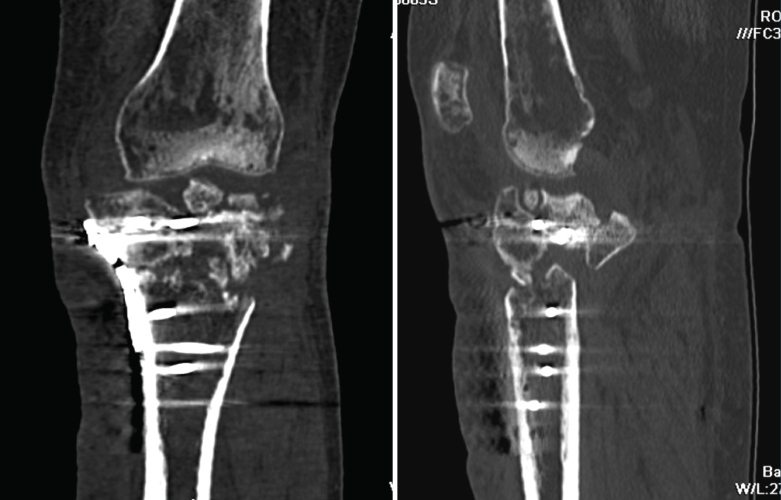

1.2. Tibia (Figura 20)

Figura 20. Corte de reconstrucción coronal de tomografía axial computarizada de rodilla: fractura de ambas mesetas tibiales.

La pseudoartrosis se define cuando, transcurridos al menos 6 meses desde la fractura, no se produce su consolidación y se evidencian muy pocos o ninguno de los signos de evolución radiográfica (Figura 22).

Figura 22. Corte de reconstrucción coronal y sagital de tomografía axial computarizada de rodilla: fractura metafisoepifisaria tibial sin consolidación después de 6 meses.

2.3. Retardo de la consolidación

El retardo de la consolidación es un enlentecimiento de la velocidad esperada (de 3 a 6 meses) del proceso de consolidación de una fractura, pero esta llegará a producirse de forma normal y definitiva (Figura 23).

Figura 23. Corte de reconstrucción coronal y sagital de tomografía axial computarizada de rodilla: fractura de epífisis proximal tibial con puente óseo insuficiente por retraso de la consolidación.

2.4. Consolidación viciosa

Se produce cuando los fragmentos consolidan en mala posición, con deformidades que alteran el eje del miembro inferior (Figura 24).

Figura 24. Corte de reconstrucción sagital y coronal de tomografía axial computarizada de rodilla: consolidación viciosa de la epífisis tibial proximal.